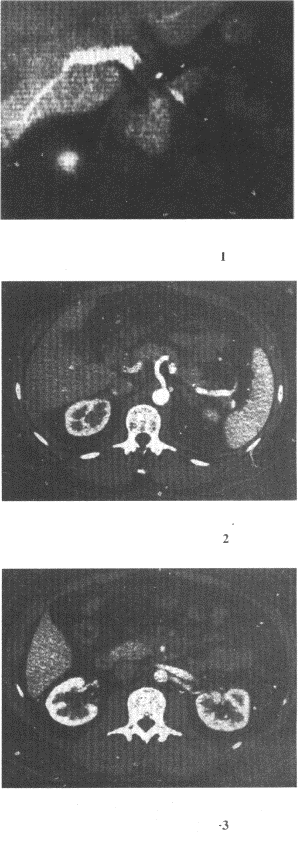

11.男,40歲,半年前因雙下肢麻木、發涼、疼痛于外院診斷血栓閉塞性脈管炎,近1周腹痛、腹脹,以中下腹為著,呈陣發性加劇就診,行CT增強掃描,如圖所示,下列描述正確的是

正確答案:ABCE 解題思路:ABCE均符合圖像改變,考慮為門靜脈及腸系膜內血栓形成。